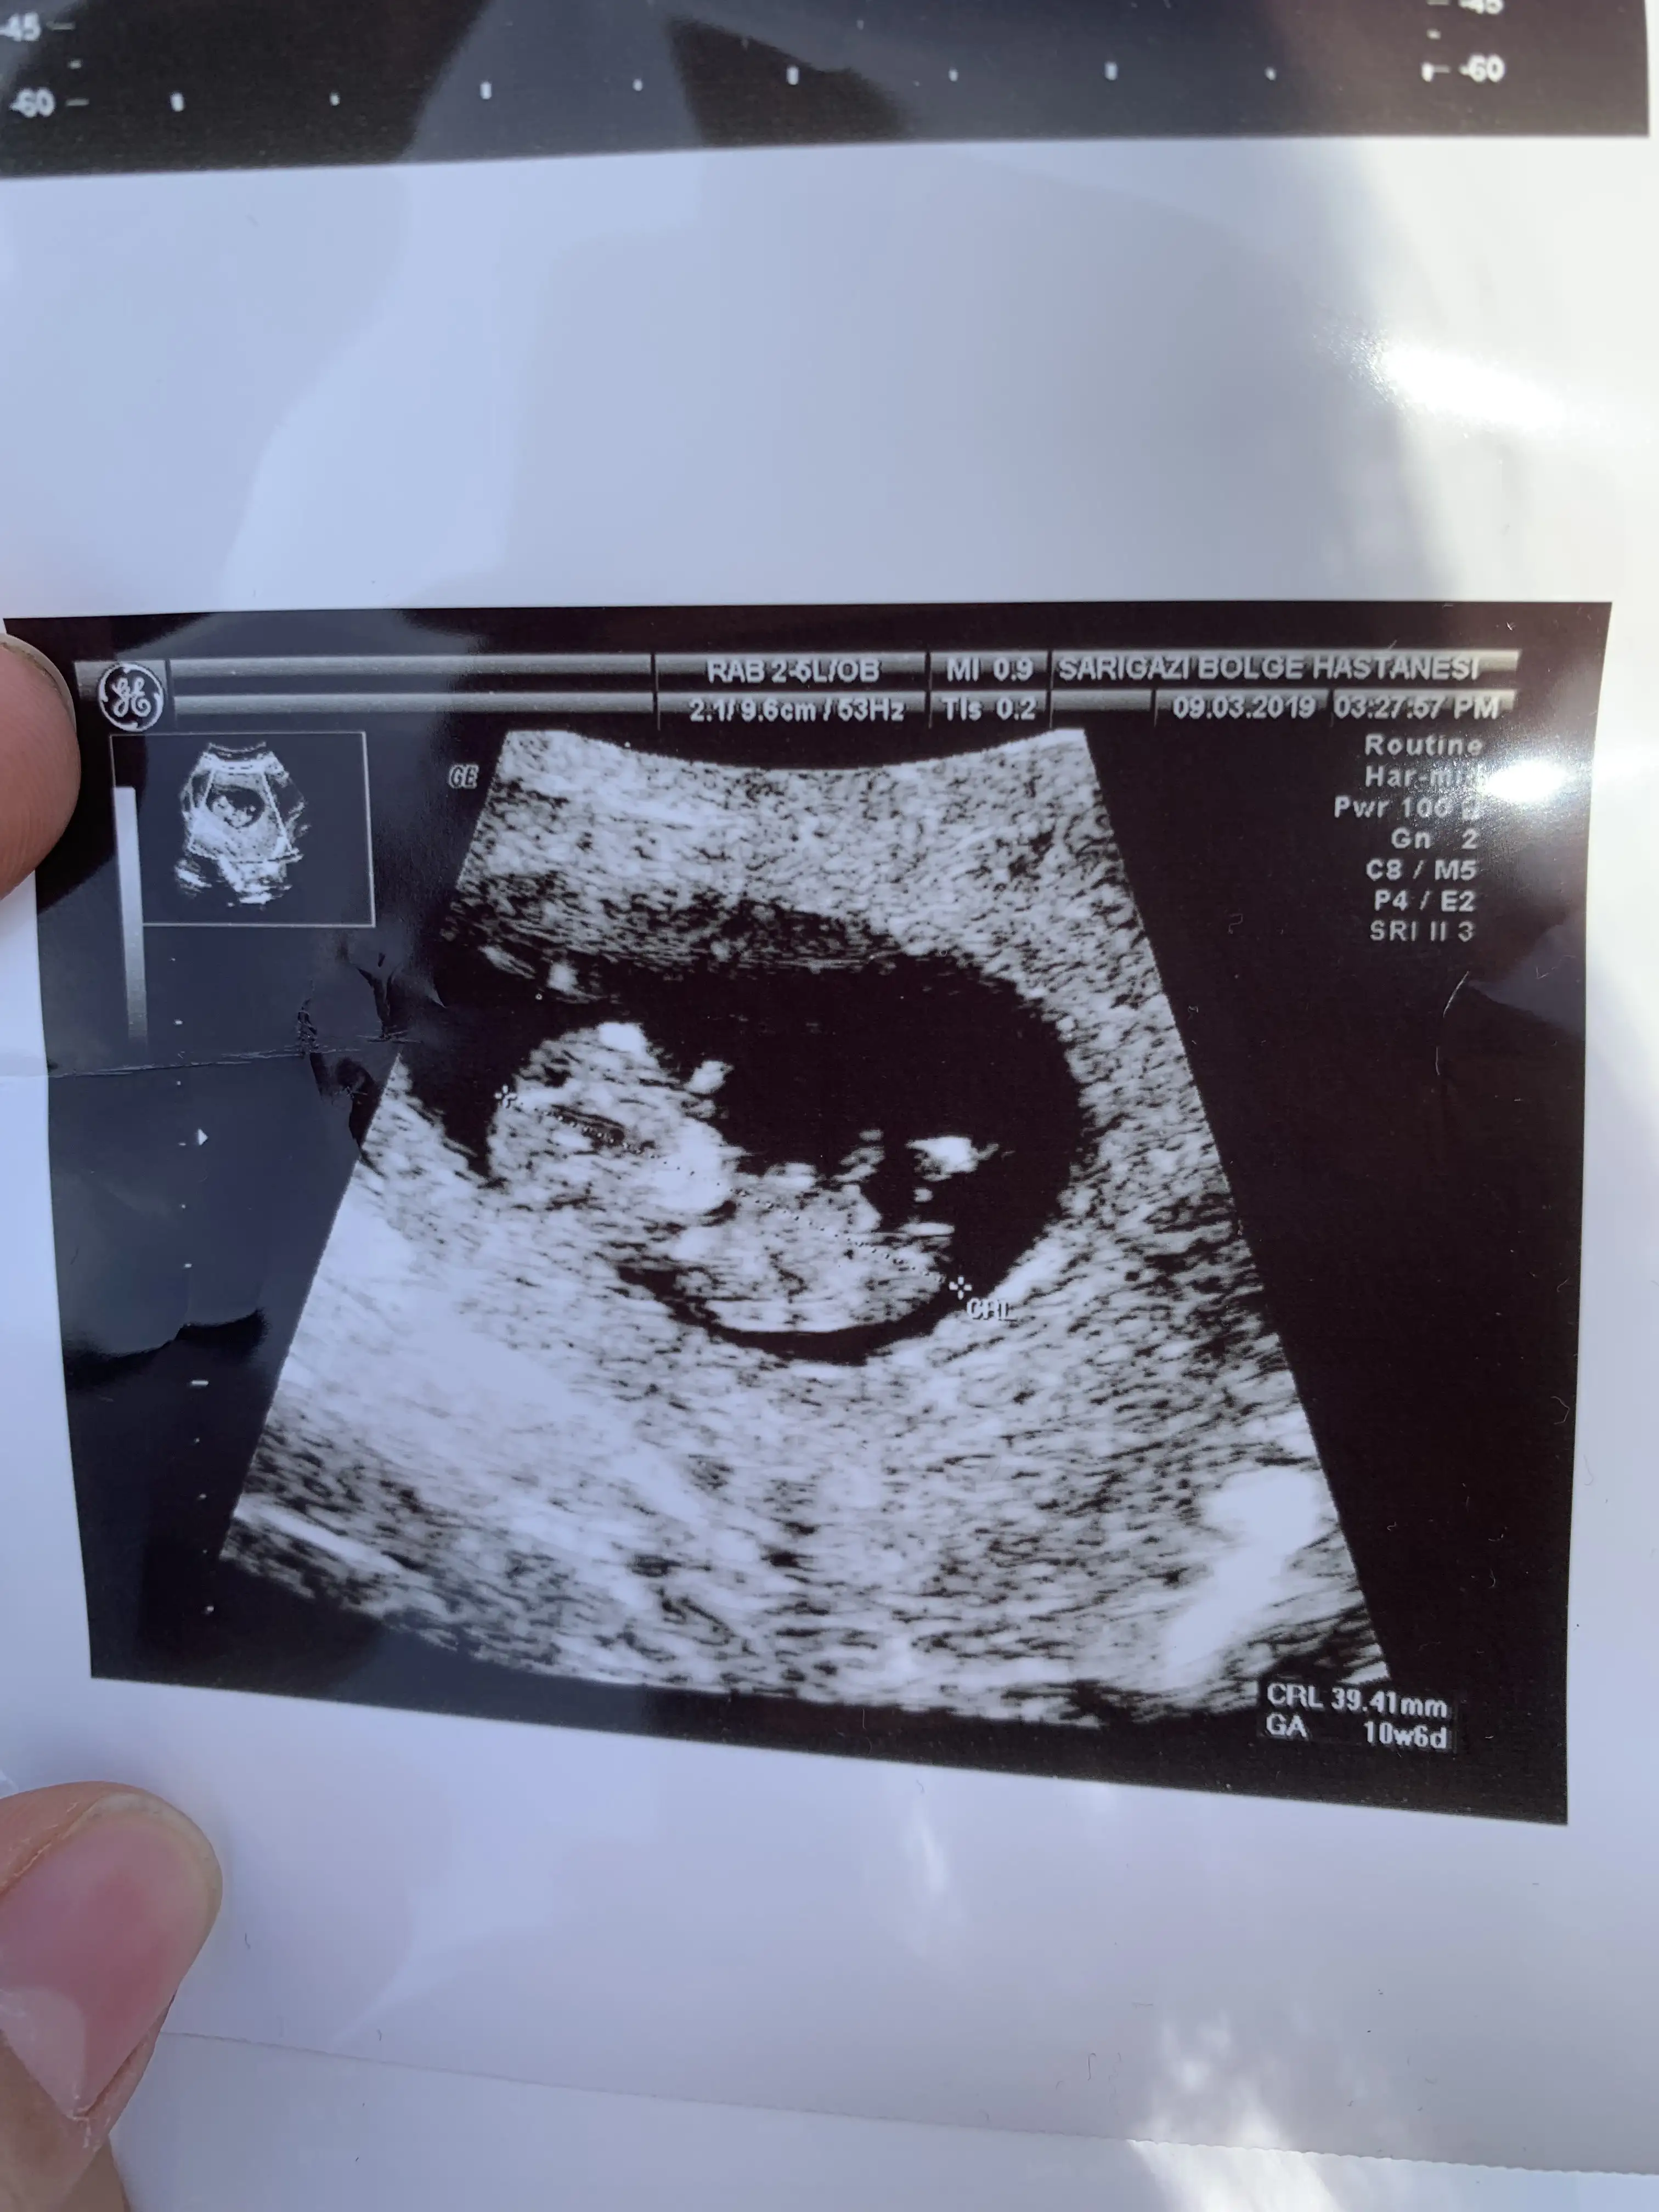

2 hafta önce 10 hafta falan olması lazımYeni mı yedin cnm kaç haftaliktn

Anladım cnm2 hafta önce 10 hafta falan olması lazım

Ayyy ne şirin yaaa maşallah ellerini kaldırmış böööö yapıyo sankiEkledigimden emin olamadim..arrtik direk foto atabiliyormusuzzz :) Cok komik degil mi ya :)))resmen poz verdi cingöz.

Ekledigimden emin olamadim..arrtik direk foto atabiliyormusuzzz :) Cok komik degil mi ya :)))resmen poz verdi cingöz.

Tam bir sayko ya :))) esim bakip bakip bu kiz degil yaaa diyo hahahaha :)))) benim gozlerde iri bu da iri gozlu sanirsam :)) ne degisik bir sey ya sana benzemesi..Ayyy ne şirin yaaa maşallah ellerini kaldırmış böööö yapıyo sanki